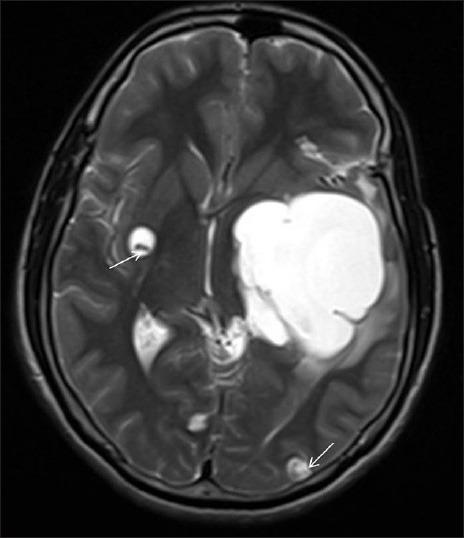

Giant racemose neurocysticercosis with mass effect: Unusual presentation.